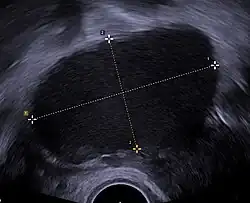

Transvaginal ultrasonography showing a 67 x 40 mm endometrioma as distinguished from other types of ovarian cysts by a somewhat grainy and not completely anechoic content.